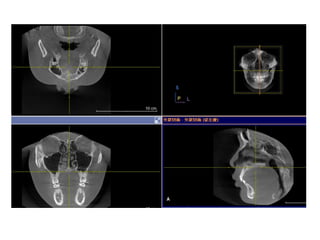

• 46.

• 62.

• 63.